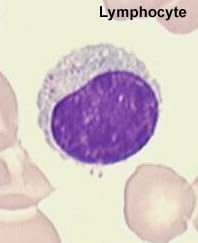

Dans les ganglions lymphatiques se trouvent réunis dans un microenvironnement, les différents acteurs des réponses immunitaires. C'est au sein de cet espace ganglionnaire que va s'initier la réponse immunitaire acquise au cours d'une action synergique des leucocytes.